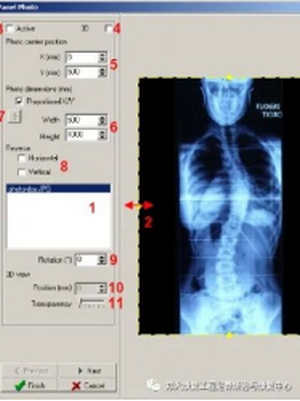

1.脊柱侧弯筛查需站立位全脊柱X光片正侧位。

2.骨盆前倾:矢状面 Cobb 角>50°。